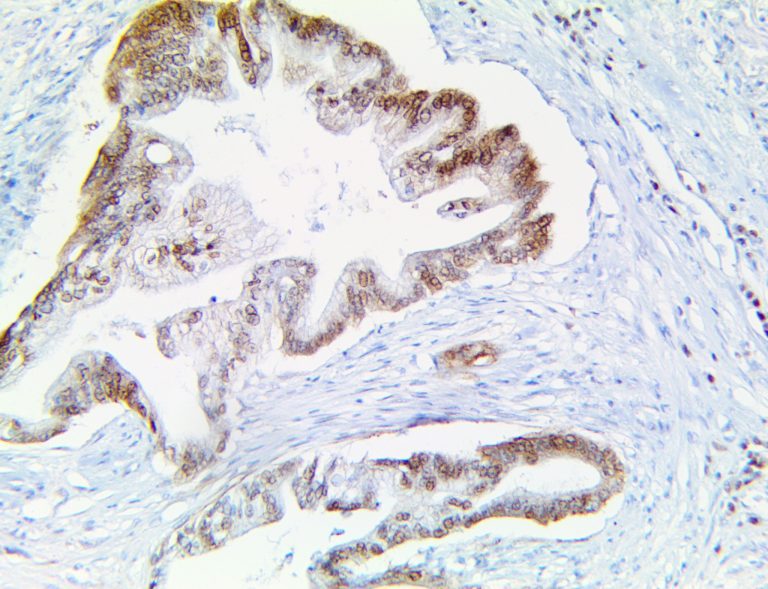

The first cytokines released are interleukin 1β (IL-1β) and tumor necrosis factor-α (TNF-α), which attract a variety of circulating white blood cells (WBCs) to the infection site, including neutrophils, monocytes, macrophages, and natural killer (NK) cells. This response, along with the antipathogenic chemicals released by these cells (i.e., complement), comprise the innate immune response. These cells directly attack the invading pathogen and also release additional cytokines, chief among them interleukin-1 and 6 (IL-6). IL-6 is essential for invoking the adaptive immune response, which calls T-cells, B-cells, and T helper (Th) cells to the infection site. IL-6 also stimulates further recruitment, proliferation and activation of macrophages.

This activation induces inflammatory monocytes to highly express IL-6, starting a localized and then systemic cascade effect that results in hyperproduction of IL-6, which accelerates the inflammatory process. Because IL-6 also increases vascular permeability, excessive levels cause blood vessels to become very leaky. This, along with clotting factors released from vascular endothelial cells, stimulates the coagulation cascade, resulting in microthrombosis (tiny clots), which leads to ischemia and tissue death of the kidney, intestines, heart, liver, brain and extremities.